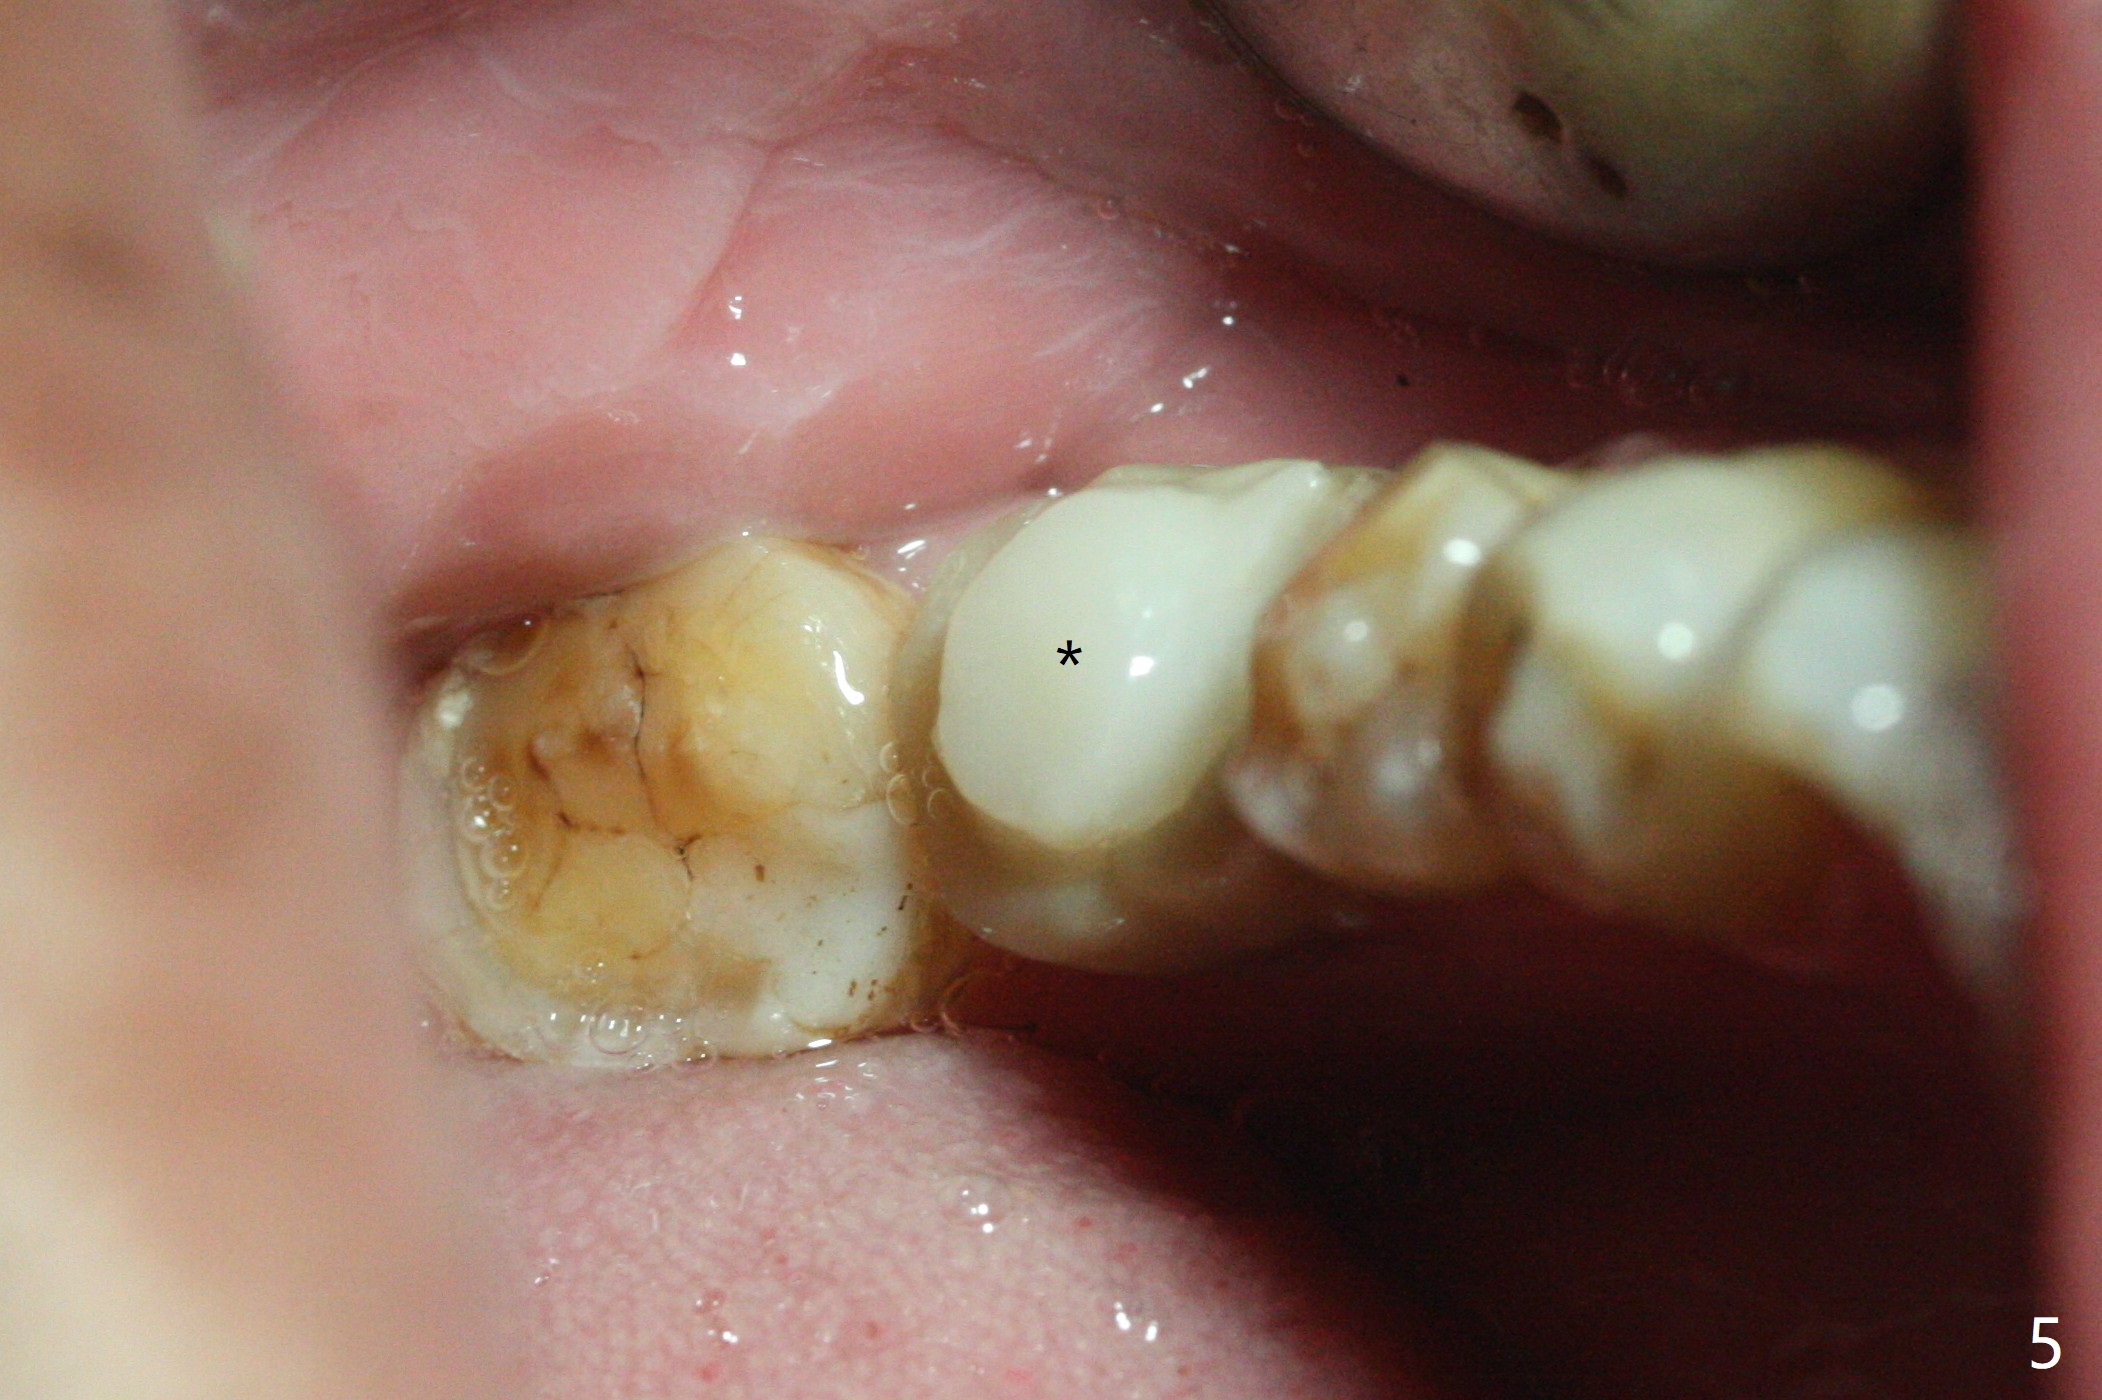

A 62-year-old man complains of food impaction around #19 implant crown one year 4 months post cementation (Fig.1-3). Before redo of the crown with poor mesial emergency profile (Fig.3 *), it appears necessary to correct the supraerupted opposing molar (Fig.1-3 downward arrow) and mesially tilted 2nd molar (Fig.3 horizontal arrow). The tooth #19 had been missing 20 years before implantation, associated with occlusal wear at #18 (Fig.4). For intrusion, composite is placed in the occlusal surface of #19 crown after roughening (Fig.5,6) with occlusal separation of the remaining dentition (Fig.6). The patient is instructed to bite on the left side as much and long as possible (even when he does not eat). Will the tooth #14 be intruded? Is the treatment sufficient?